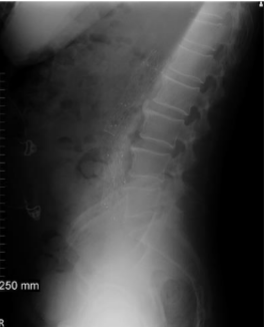

Projection?

Upright abdomen

In an AP Abdomen upright, the CR enters at the level of

2 inches above iliac crests

On an AP Abdomen upright, air seems to be in a ____ manner

horizontal